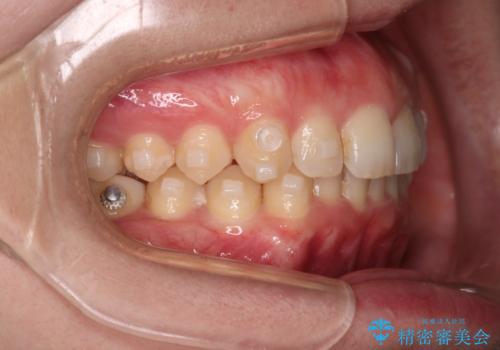

- インビザライン・ワイヤー装置(クリア装置)

右側臼歯部の咬合改善のために、臼歯部のみ部分的なワイヤー矯正を行い、咬合改善がみられてからインビザラインにて全体的な矯正を行なっていく治療計画を立てました。

噛み合わせをよくするために、ワイヤー矯正とインビザライン矯正のどちらの期間も必要な箇所にゴム掛けを行いながら治療を行いました。